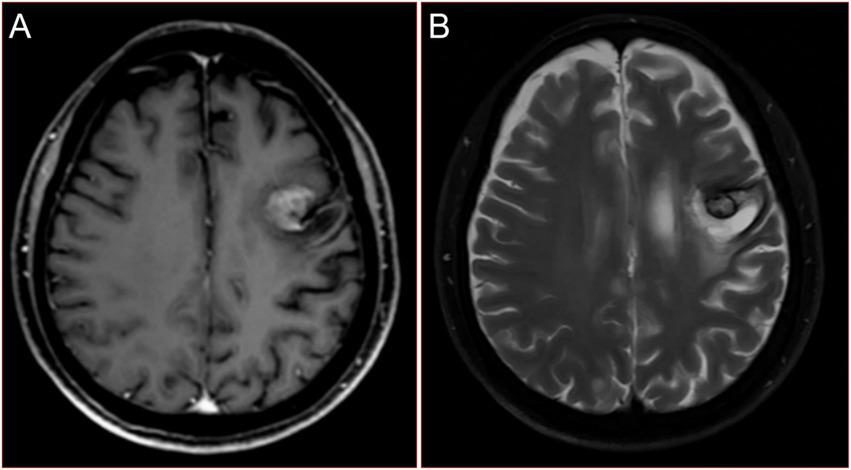

Given that the patient had no history of fever and no special abnormalities in the results of laboratory tests, the multidisciplinary team (MDT) suggested that lung metastases or lung malignancies with intrapulmonary metastasis should be considered. A magnetic resonance imaging (MRI) examination of the head was performed and revealed brain metastatic lesion (Figures 2A,B). Unfortunately, due to financial constraints, the patient did not undergo the PET-CT examination. At the same time, he underwent gastroscopy and colonoscopy because of concerns about weight loss, but no tumor was found. Finally, a puncture biopsy of the lung lesion was performed under ultrasound guidance, and the histologic results confirmed PSC with giant-cell carcinoma (Figures 3A–C), PD-L1 (=1%, Clone: 22C3, Dako, Agilent Technologies, Inc.).

Figure 2

Magnetic resonance images of the head with the patient at admission. (A) Contrast enhanced T1WI. (B) T2WI.

He received a diagnosis of stage IVb PSC, cT4N3M1, with a negative EGFR status (as per the ninth edition TNM classification, the presence of numerous lesions in the same lung lobe is classified as T4, while the presence of nodules in the opposite lung lobe and multiple metastases in distant organs is categorized as M1. Additionally, the presence of bilateral hilar and mediastinal lymphadenopathy is classified as N3). He received recombinant human endostatin (Endostar, days 1–14: 7.5 mg/m2 every day) combined with pemetrexed (250 mg/m2 on day 1) and cisplatin (15 mg/m2, daily from days 1 to 3). During this treatment, the patient experienced some common side effects, such as nausea, fatigue, infections, vomiting, decreased appetite, decreased red blood cell count, decreased platelet count, and decreases in the components of white blood cells, which were successfully alleviated with conventional methods. After two cycles of chemotherapy, there was no significant improvement in his symptoms. Reexamination of the head MRI showed that the metastatic tumor had become smaller (Figures 4A,B), but the chest X-ray showed no significant improvement in the lung lesions. Then he encountered a new wave of the COVID-19 pandemic. When he was taken to the hospital after being infected, his face was blue, and he had severe breathing difficulties. A blood oxygen saturation test showed that his peripheral blood oxygen saturation was only 72%. The doctor recommended ventilator treatment with endotracheal intubation, but the patient’s family refused to allow it, citing the patient’s prior wishes. Unfortunately, he died that day. His family refused further autopsy.